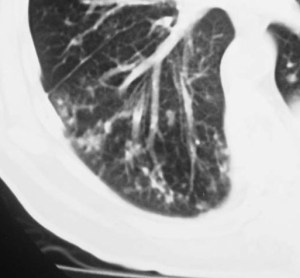

SIGNO DE LA CISURA INCOMPLETA, DE LA PSEUDOCAVIDAD O SIGNO DE LA ESPINA DE ROSA

Es un signo de derrame pleural en la cisura mayor visible en la radiografía de tórax, en un paciente con cisura mayor incompleta. Es más frecuente verlo en el lado derecho ya que en el izquierdo la silueta cardiaca puede ocultarlo.

La presencia de una zona radiotransparente perihiliar, circunscrita lateralmente por una línea curva bien marcada (flecha blanca), en cuya periferia se observan varios grados de opacidad, corresponde a la presencia de líquido en la cisura mayor incompleta. La línea curva termina en un extremo en punta (flecha roja), que estará más cercana al hilio cuanto más completa sea la cisura.

El nombre de pseudocavidad hace referencia a la radiolucencia perihiliar, mientras que el de espina de la rosa se refiere a la morfología de la opacidad, con el extremo en punta.